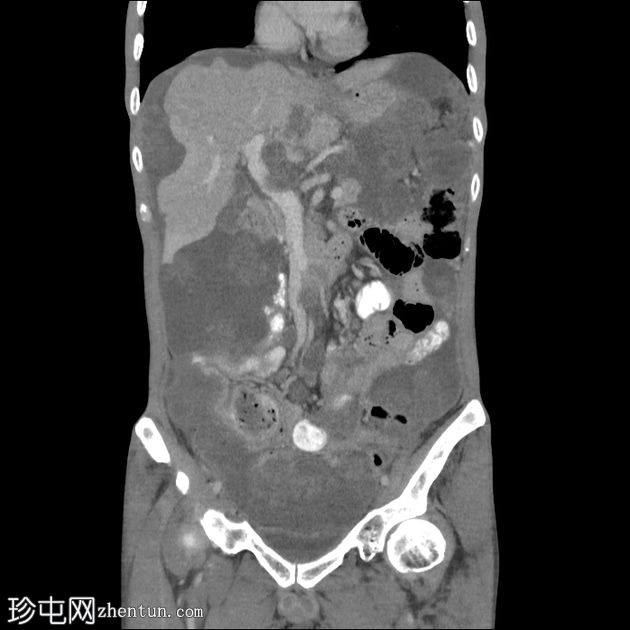

冠状位增强扫描(门静脉期)

大网膜和肠系膜内可见低密度、不均匀的腹膜积液,脏器表面呈扇形凹陷,尤其以肝脏和脾脏最为明显。

直肠穹窿可见一处厚度 1.2 cm、长 4.0 cm 的增强壁增厚。可见病灶周围及骶前淋巴结肿大,最大者直径 1.6 cm。

可见双侧少量胸腔积液(右侧:1.0 cm;左侧:0.2 cm),右下后基底段被动性塌陷。